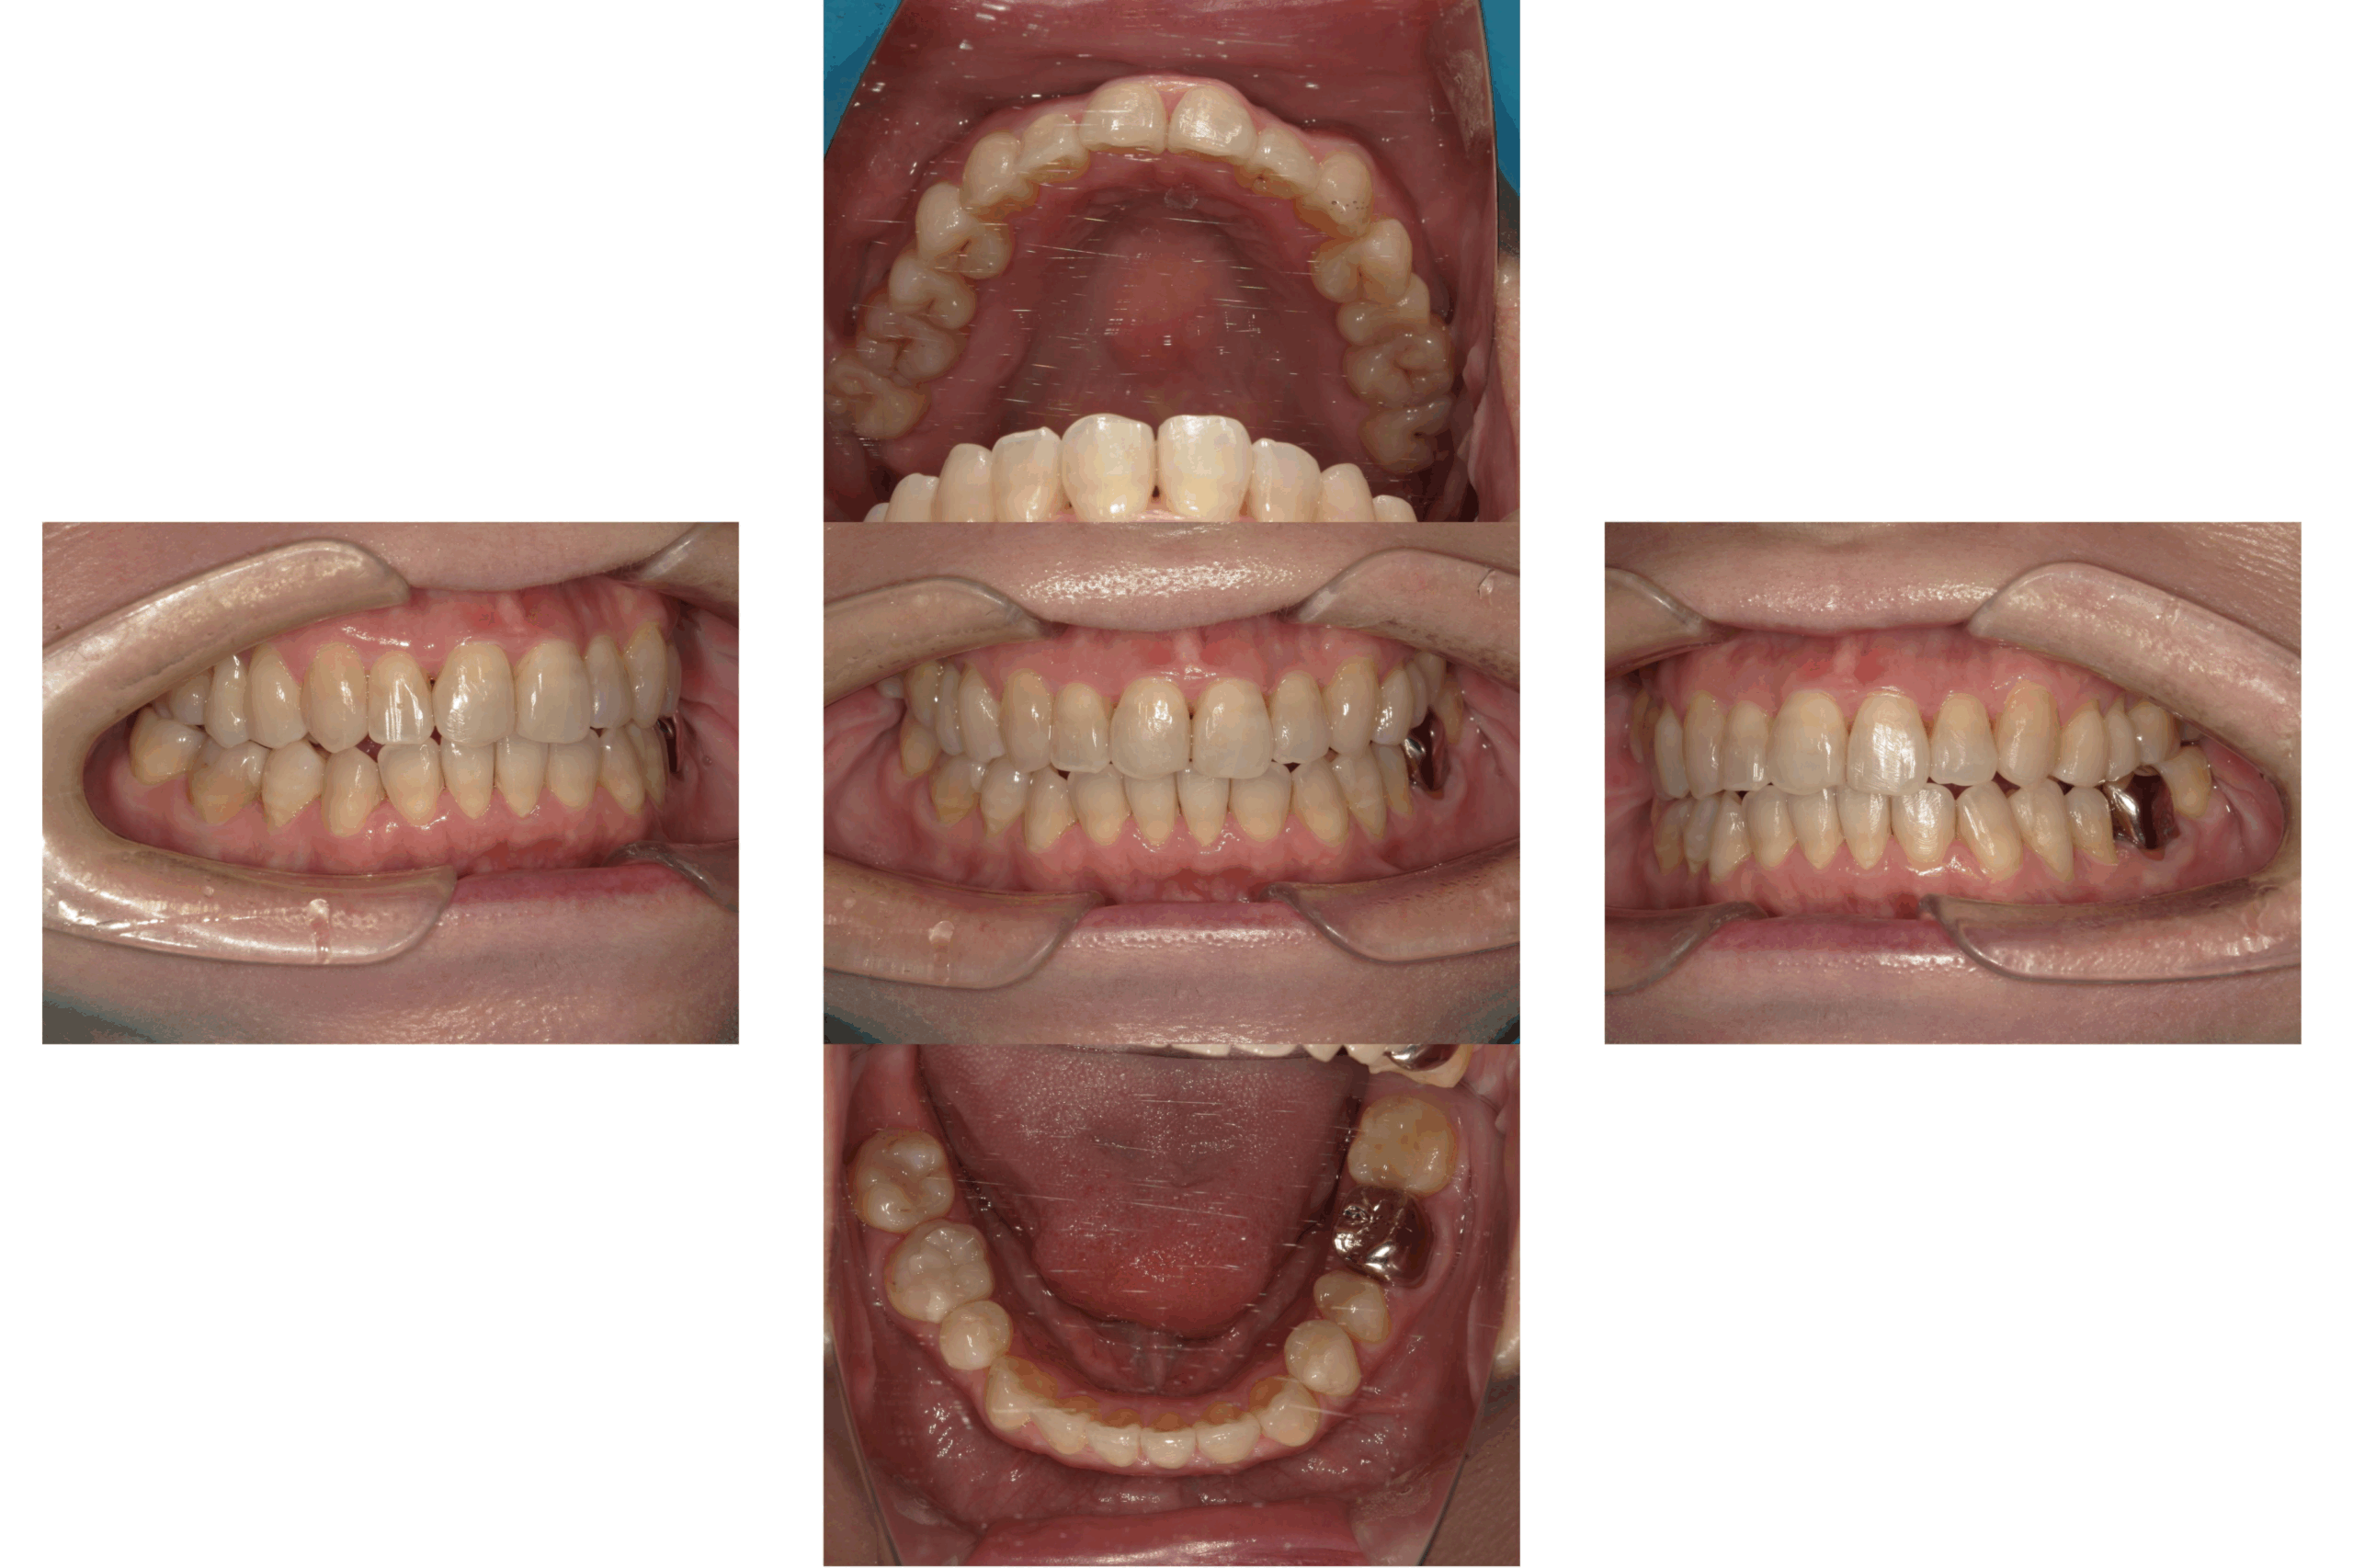

インプラント

Before

After

年齢

65歳

主訴

奥歯で硬いものが噛めない

治療期間

約6ヶ月

治療費

約1,500,000円

概要

奥歯で固い食べ物が噛めず、年齢とともに噛み合わせや咀嚼機能の低下を実感されていました。

インプラント治療を行うことで、噛む力の回復・機能改善が期待できると判断しました。

患者様と相談のうえ、骨の状態や全身の健康状態に配慮しながら治療計画を立て、骨造成を行い、インプラント体を安全に埋入。その後、人工歯(上部構造)を装着しました。

治療後は、硬い食事もしっかり噛めるようになり、「食事の楽しみが戻った」と喜んでいただけました。

リスク

外科手術を伴うため、腫れや痛み、内出血が生じる場合があります。

骨量が不足している場合、骨造成(GBRやソケットリフト等)の追加処置が必要となることがあります。

インプラントが骨と結合しない場合、再手術や撤去が必要となることがあります。

メンテナンス不足や清掃不良により、インプラント周囲炎(歯周病のような症状)が起こる可能性があります。

喫煙・全身疾患・噛み合わせの状態により、治療結果に影響が出る場合があります。

長期的な安定のためには、定期的なメンテナンスとセルフケアが必須です。